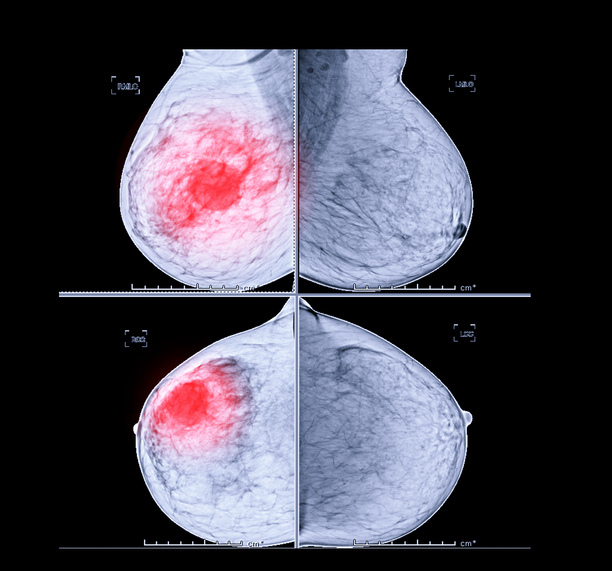

하지만 유방암이 의심되는 유방 분비물의 증상은 한쪽 유방에서만 나옵니다. 그리고 붉은색, 갈색과 같은 피색깔이 나옵니다. 유방암까지는 아니더라도 유방암으로 발전할 수 있는 유두종 같은 고위험 병변의 가능성 또한 있기 때문에 이러한 증상이 나타날 경우에는 반드시 유방 초음파 검사와 엑스레이 검사를 받으셔서 확실한 병변을 구분하셔야 합니다.